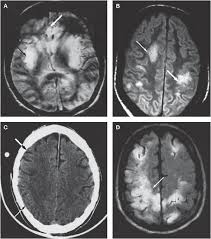

Herpes simplex virus (hsv) encephalitis hsv encephalitis (hsve) is the most common cause of infectious encephalitis (1); Initially clinical and brain mri findings were in favor of herpes simplex virus (hsv) encephalitis. The laboratory diagnosis of autoimmune encephalitis. Acute hsv encephalitis who had neuroimaging repeated within four weeks of the first scan. • occurs despite blood brain barrier with tight junctions.

The laboratory diagnosis of autoimmune encephalitis. The study analysed serially acquired magnetic resonance images (mri), of patients with acute hsv encephalitis who had neuroimaging repeated within four weeks of the first scan. Associated with hsv encephalitis (strong evidence). Its symptoms are fever, confusion, coma, and seizures. A case of granulomatous hsv encephalitis: Having said that, mri with contrast is considered the most sensitive imaging modality, and findings are present in over half of individuals 8. Severe infection, particularly untreated herpes simplex virus (hsv) encephalitis, can cause brain hemorrhagic necrosis. Herpes simplex encephalitis occurs as 2 distinct entities:

It is a severe condition brain mri may show limbic encephalitis (55) or diffuse t2 and dwi hyperintensities in the white matter, associated with restricted diffusion (54). Brain mri—increased t2 signal intensity in frontotemporal region → viral (hsv) encephalitis. Associated with hsv encephalitis (strong evidence). Provided cranial imaging has excluded any contraindications such as a space occupying lesion or severe cerebral oedema and brain shift, a csf. Having said that, mri with contrast is considered the most sensitive imaging modality, and findings are present in over half of individuals 8. In addition, because of the involvement of the. We performed volumetric measurements of the left and right temporal lobes and of cerebral oedema. Herpes simplex encephalitis occurs as 2 distinct entities: The study analysed serially acquired magnetic resonance images (mri), of patients with acute hsv encephalitis who had neuroimaging repeated within four weeks of the first scan. Pregnancy the most common cause of encephalitis in newborns is vaginal delivery from a mother who is infected with herpes simplex virus 2 (hsv 2). There is no particular age, sex, or seasonal predilection. Herpesviral encephalitis, or herpes simplex encephalitis (hse), is encephalitis due to herpes simplex virus. Severe infection, particularly untreated herpes simplex virus (hsv) encephalitis, can cause brain hemorrhagic necrosis.

The patient had initially improved after medical treatment. The study analysed serially acquired magnetic resonance images (mri), of patients with. • occurs despite blood brain barrier with tight junctions. Clinical, magnetic resonance imaging, and electroencephalographic findings in paraneoplastic limbic encephalitis. Alpha coma in japanese encephalitis. Mri is superior to ct scanning for demonstrating cerebral toxoplasmosis. Hsv pcr and other infectious studies from the serum and csf were negative. Brain mri is shown in fig.